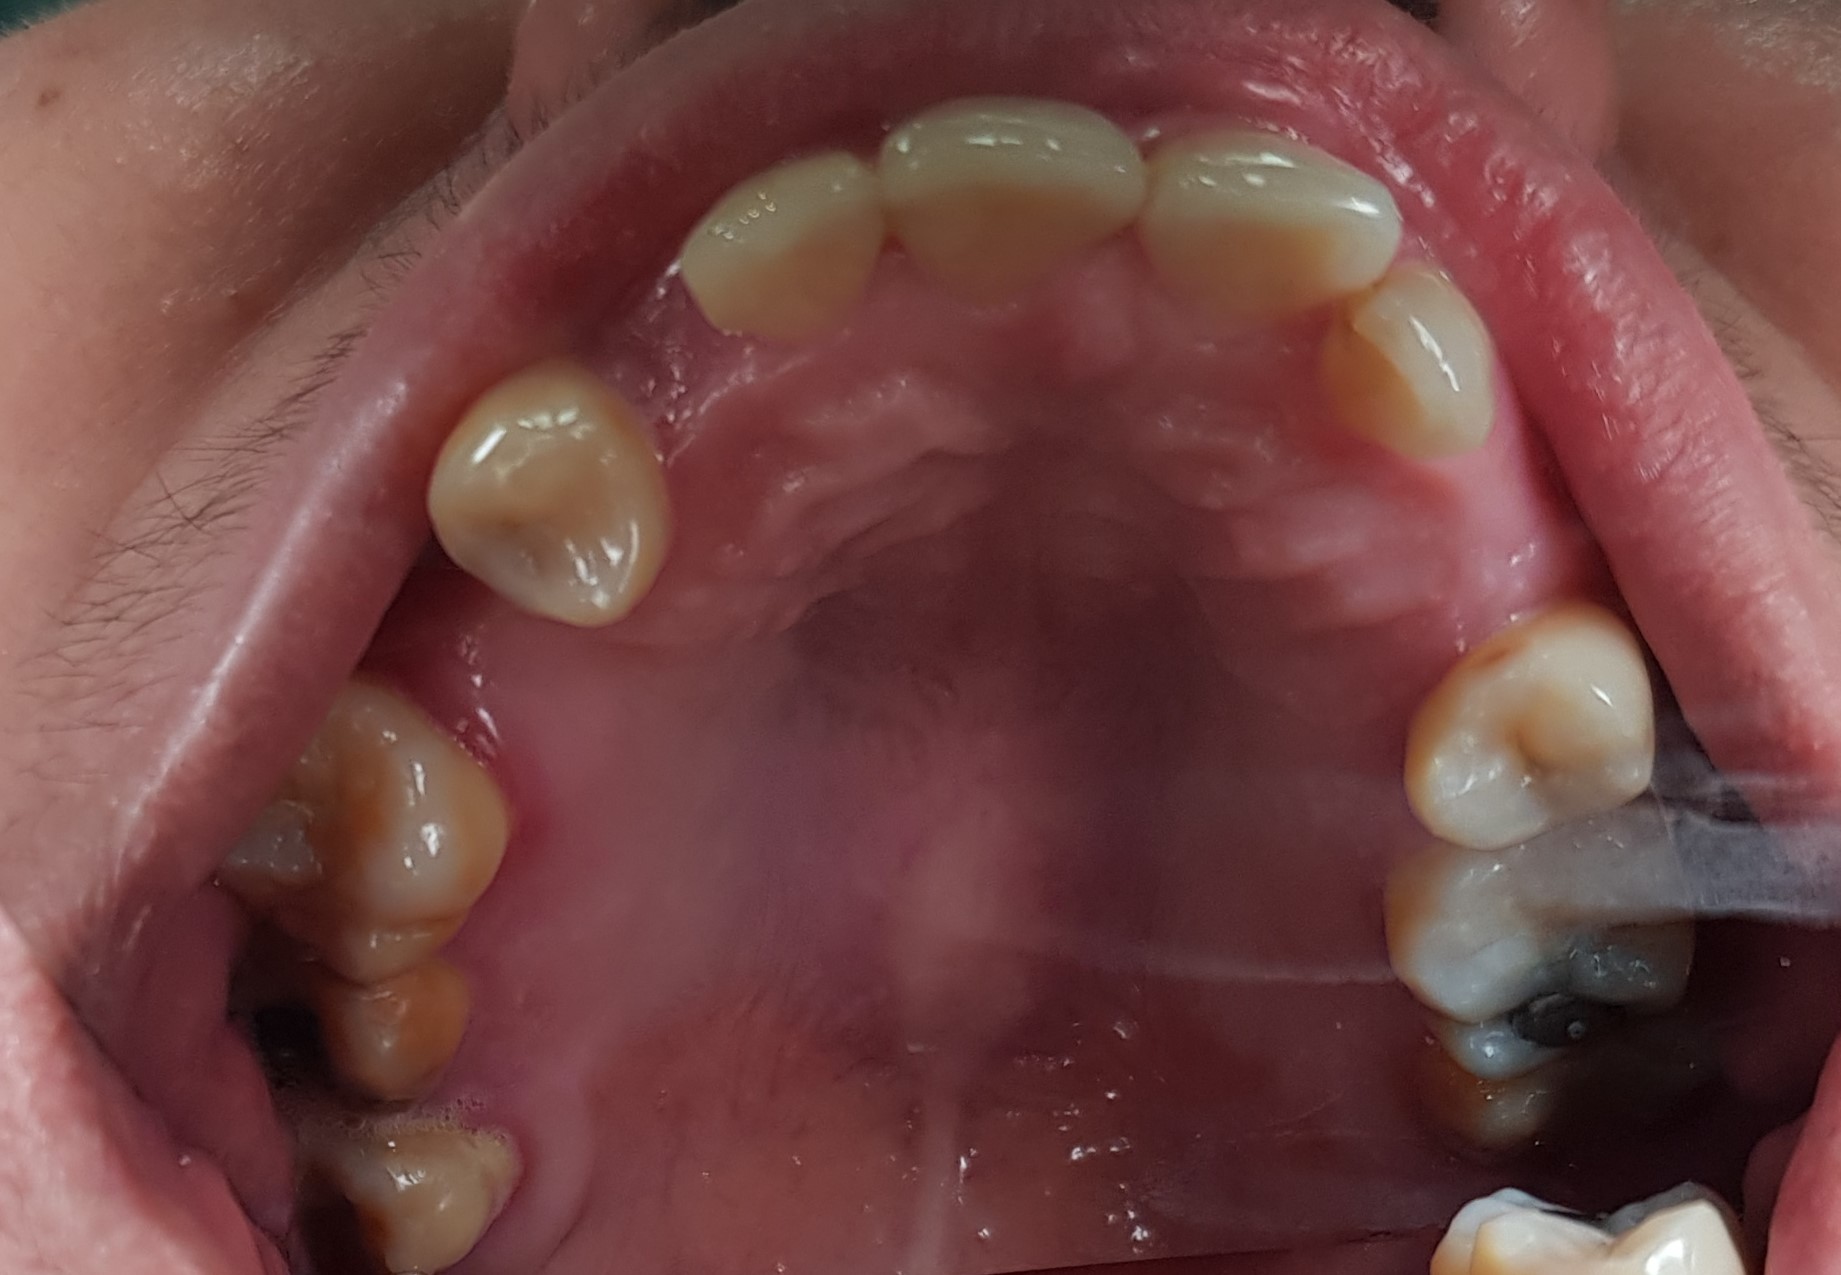

Abstract: Removable partial denture is a definitive prosthesis that has been used in dentistry for decades for the rehabilitation of partially edentulous patients. The visibility of the retentive arm in the metal denture sometimes causes esthetic problems for the patient. Therefore, aesthetic aspects should be considered to ensure patient satisfaction in dental treatment. This case report described oral rehabilitation using a combination of metal frame partial denture and thermo-plastic. A 40-year-old female patient with a history of old removable partial denture came to replace the old denture with a new one that was more aesthetic and showed no wire. The management of the patient included thorough anamnesis, extra and intra oral examinations, anatomic impression, determination of definitive treatment, preparation of rest on the abutment tooth, physiological impression, manufacturing of metal frameworks in the upper and lower jaws, determination of definitive vertical dimension, try-in denture, insertion, and control of combination of a metal frame partial denture with thermoplastic in the upper and lower jaws. The patient was satisfied with her new denture.  In conclusion, the combination of a metal frame partial denture with thermoplastic can be an alternative treatment for patient who wants to replace his/her missing teeth with removable partial denture while still prioritizing aesthetic factors.